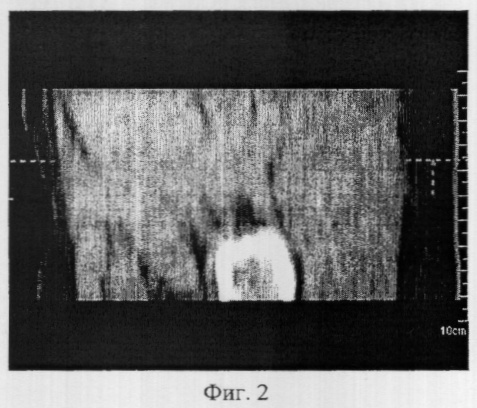

Фиг.2 иллюстрирует направление плоскости аксиального среза по отношению к ходу мышечных пучков мышц ягодичной области;